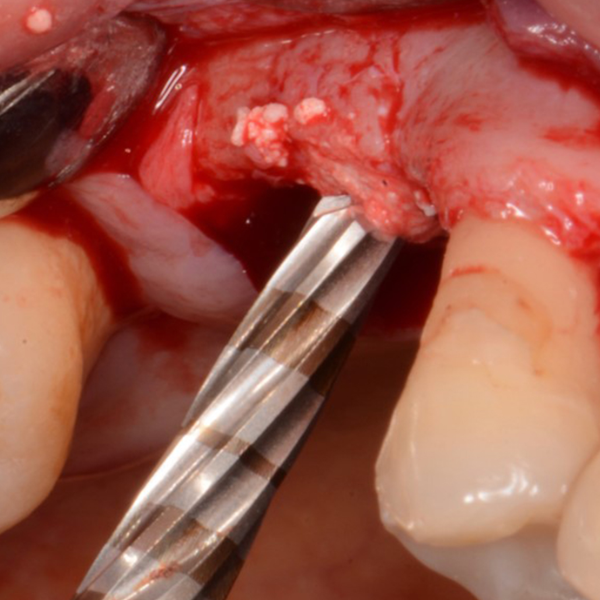

Removal Of Implant, Sinus Lift And Implant Replacement